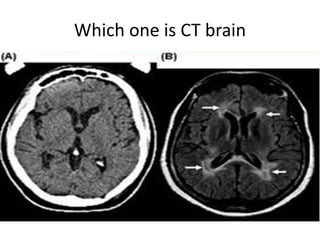

Which one is CT brain

How to differentiate CT from MRI

• Bone is dense(white) on CT brain while hypo

intense(dark) on MRI(outer bright signals on

MRI are due to subcutaneous fats).

• Grey-white matter differentiation is clear on

MRI compared to the CT.

• Presence of periventricular lucent areas in

MRI.

• MRI usually have multiple films compared to

commonly single in CT

Which one isCT brain

How to differentiateCT from MRI • Bone is dense(white) on CT brain while hypo intense(dark) on MRI(outer bright signals on MRI are due to subcutaneous fats). • Grey-white matter differentiation is clear on MRI compared to the CT. • Presence of periventricular lucent areas in MRI. • MRI usually have multiple films compared to commonly single in CT